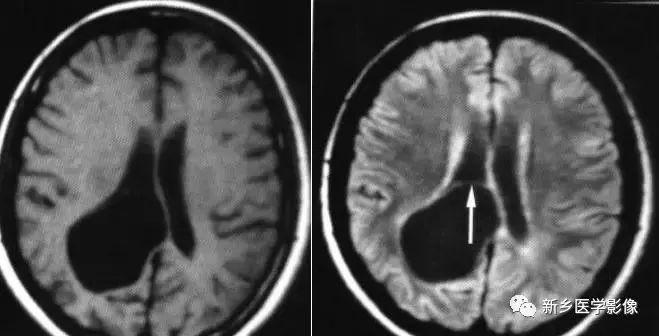

脑裂畸形:

脑裂畸形发生在胚胎期神经元移行阶段。脑裂畸形可累及一侧或双侧大脑半球。脑裂畸形位于侧面,常累及中央前、后回区,偶尔位于大脑半球的其他部位。

脑裂畸形的裂隙可以很窄,裂隙两侧灰质紧密相贴,称闭合型;裂隙也可以很宽,中间为脑脊液,称分离型。

临床上脑裂畸形常表现有癫痫发作,其他神经系统症状可从很轻微到很严重.主要取决于脑裂畸形使脑组织缺损的严重程度。单侧闭合型脑裂畸形症状通常较轻,双侧分离型脑裂畸形症状较明显。